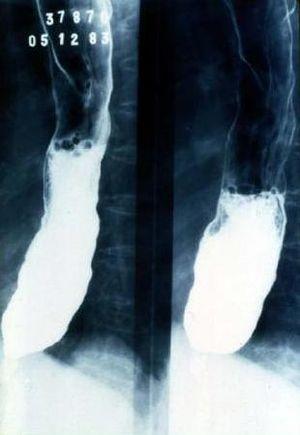

Chagas megaseophagus.JPG

Chagas megaseophagus